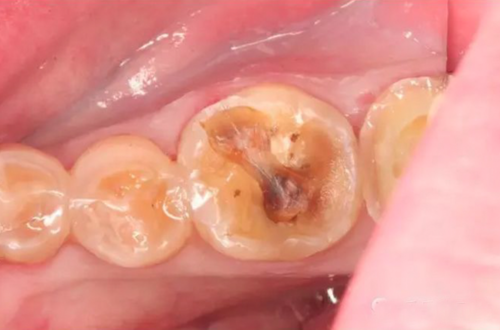

图1:下牙槽神经从下颌骨中穿出

在手术中进行翻瓣以暴露第三磨牙时,遇到了一些阻力。经过仔细检查,发现一根与骨膜瓣粘连的绳索状结构。将其轻轻分离后,确认该结构为下牙槽神经。该神经在距离口腔皮质骨外侧1.5厘米处穿出,且没有骨组织覆盖,随后重新进入下颌骨。